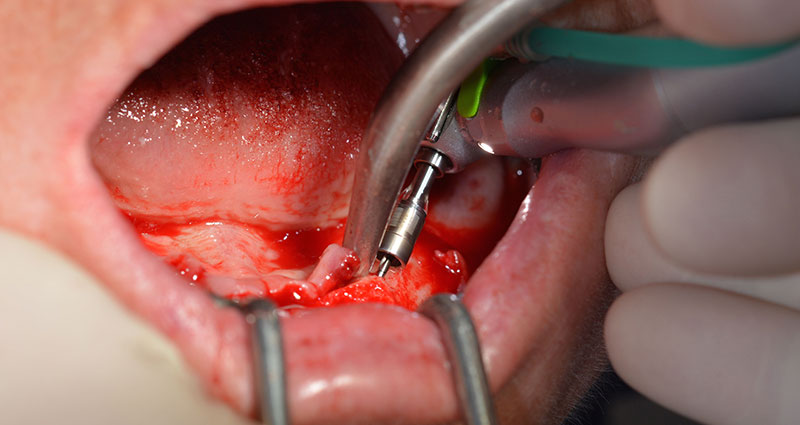

Tras la extracción de la dentición residual en el maxilar inferior, se realizó la incisión crestal en la región comprendida entre la pieza dental 37 y la 47.

A continuación, se identificó el agujero mentoniano (foramen mentale) como la estructura anatómica límite y se alisó el cortical de la cresta ósea con la pieza de mano recta y una fresa redonda grande (fig. 4).

dentición residual

Fig. 4